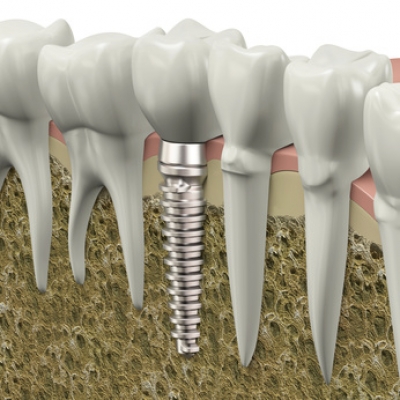

İmplant kaybedilen diş kökünün yerine çene kemiğine yerleştirilen, titanyum malzemesinden üretilmiş küçük bir parçadır. İmplant ayakta tedavi kapsamında lokal anestezi altında yapılan bir operatif işlemdir. Günümüzde yapay diş kökleri diş hekimleri tarafından hemen hemen her boşluğu doldurmakta kullanılabilmektedir.

Bir diş boşluğunu doldurmak için implant kullanıldığında komşu dişlere zarar görmeyerek doğal diş yapısının bozulması engellenir.

İmplantlar çiğneme kuvvetlerini çene kemiğine ileterek kemiğin erimeden kalmasına yardımcı olur.

Tek diş eksikliklerinin implant ile tedavi edilmesi, köprü ile restore edilmesine göre daha koruyucu bir tedavi şeklidir.

Köprü protezi yapılabilmesi için sağlıklı dişlerin küçültülerek üzerlerinin kaplanması gerekecektir ve bu köprünün belirli aralarla değiştirilmesi ekonomik olarak da bir yük getirecektir. Bunun yerine eksik diş veya dişlerin boşluğuna yerleştirilecek implantlar sayesinde yandaki dişlerde herhangi bir işleme gerek kalmadan yani sağlıklı dişlere zarar verilmeden tedavi edilebilir.